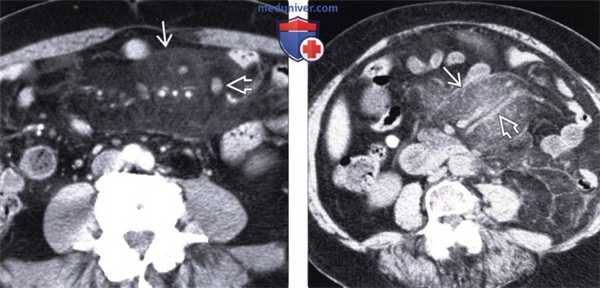

(Слева) На аксиальной КТ у пациента с болевой симптоматикой и лихорадкой определяется инфильтрация брыжейки тощей кишки, отграниченная псевдокапсулой. Визуализируются также множественные хорошо заметные брыжеечные лимфатические узлы с жировым «гало». При ПЭТ не было выявлено гиперфиксации радиофармпрепарата, симптомы регрессировали после назначения стероидной терапии.

(Справа) При аксиальной нативной КТ у пациента с длительно существующим болевым синдромом выявлена инфильтрация брыжейки тощей кишки с псевдокапсулой. Брыжеечные сосуды сдавлены, но без признаков обструкции. Все эти изменения являются проявлением и склерозирующего мезентерита.